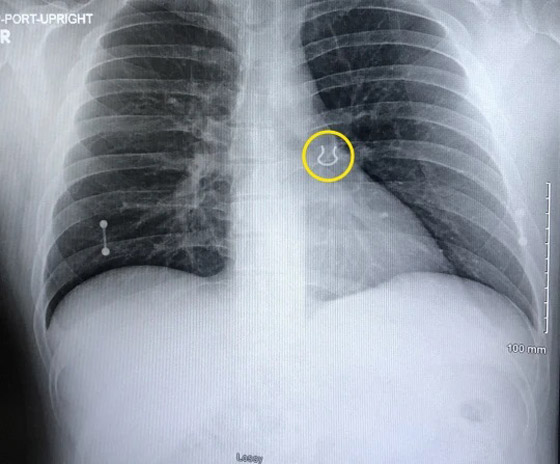

وفي المستشفى، قام الأطباء بتصوير رئتي جوي بالأشعة السينية للتحقق من الالتهاب الرئوي، وصُعقوا عندما اكتشفوا حلقة الأنف في الفص العلوي من رئته اليسرى. وقال جوي، من سينسيناتي، أوهايو، الولايات المتحدة "أجريت لي صورة بالأشعة السينية وجاء الطبيب وأظهر لي صورة الأشعة السينية وقال "هل يبدو هذا مألوفاً لك"؟

ويعرف جوي أن من الصعب تصديق قصته ما لم يكن لديك دليل، لذلك تأكد من احتفاظه بنسخ من صور الأشعة السينية وحتى صور الجراحة التي تُظهر استخراج الحلقة من داخل جسمه.